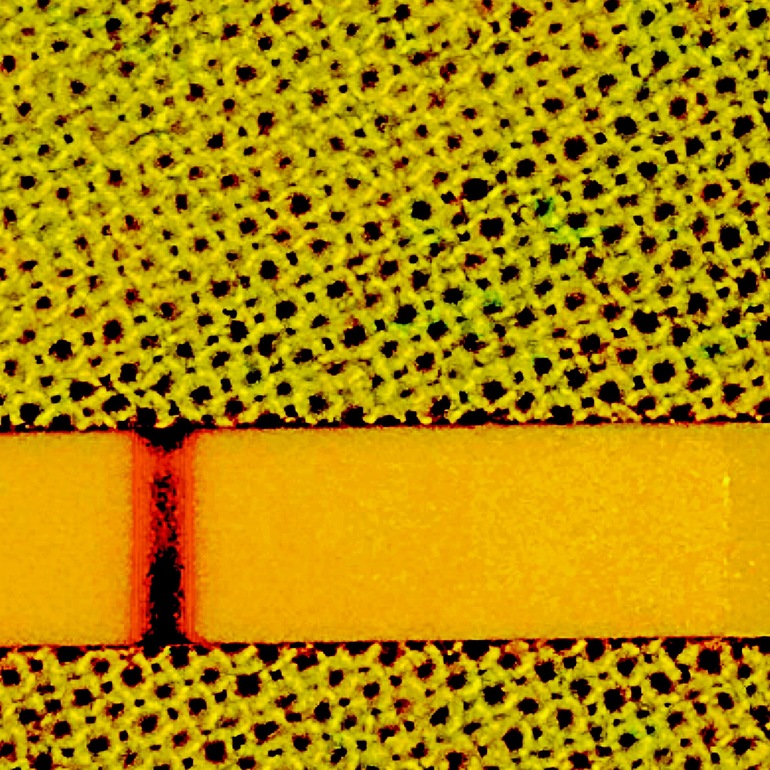

Когда фото приближаю контуры видать, реагент?

Побаловалась ещё с фоторедактором, там вообще видно и присматриваться не надо! Хоть бы оно!

На первом фото такой страшный сюр)))